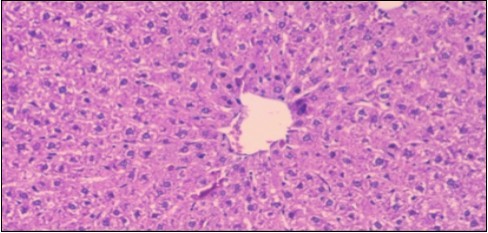

The histological examination of the livers of control rats feeding standard diet showed normal architecture hepatocytes, blood sinusoid and central vein, figure 6. The rats which were fed on a (HFD), showed swollen hepatocytes with vacuolated cytoplasm filled with fatty infiltration, congested central vein and disappearance of blood sinusoids, figure 7. By comparison, the liver of rats that were treated by fennel after obesity and control mice observed nearly normal of the hepatocytes with eosinophilic cytoplasm, central vein and clear blood sinusoids and more bi-nucleated cells, figure 8. While examination of rats' liver that were treated by Ator and after the obesity appears, they showed mild fatty change in hepatocytes, few hepatocytes retain is eosinophilic cytoplasm and central vein figure 9. Liver of rats that were treated by fennel and Ator after obesity and control rats are showing nearly normal hepatocytes figure 10.

Figure 6.Photomicrogragh of liver section of control rat showing normal architecture Hepatocytes, blood sinusoid and central vein, (H&E) (40X).